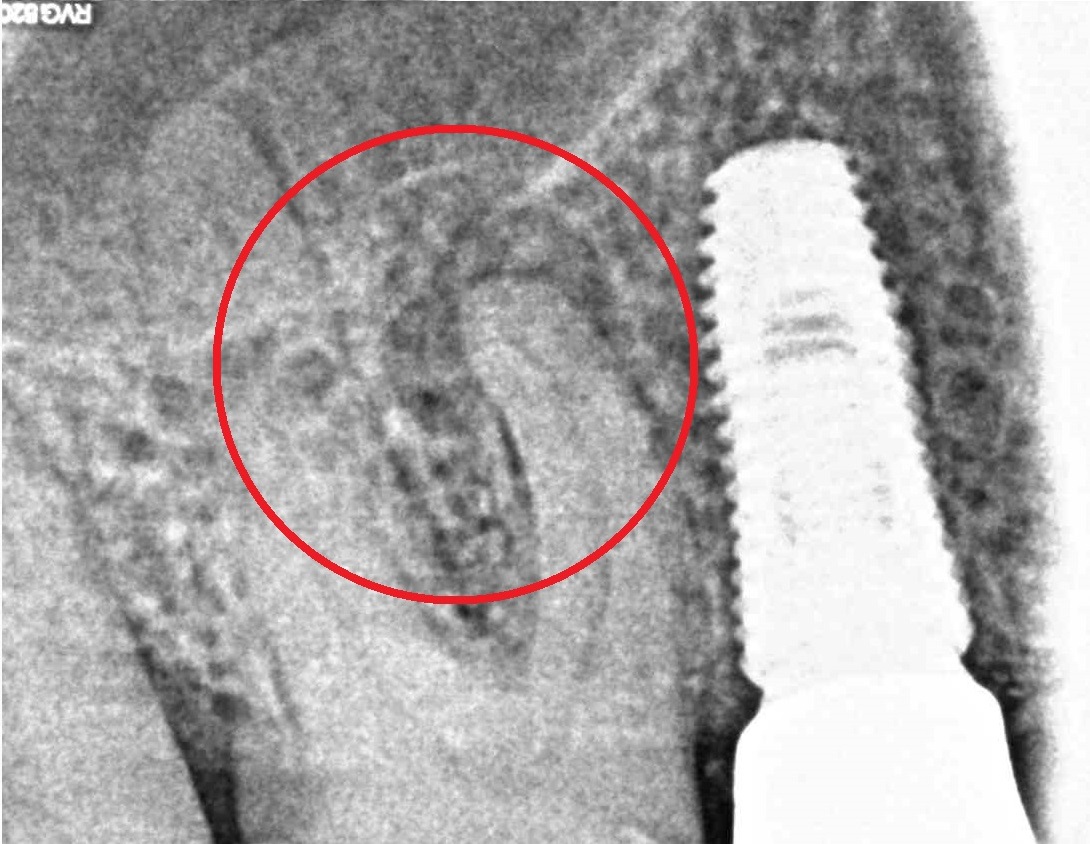

Примеры работ

- Лечение периодонтита

Проблема

Пациент обратился в клинику с постоянными ноющими самопроизвольными болями в зубе, усиливающиеся при накусывании, отечность тканей в области причинного зуба. После детального обследования были обнаружены значительные очаги воспаления на корнях зуба.Решение

Пациенту было проведено эндодонтическое лечение данного зуба. В результате лечения наблюдаем восстановление костной ткани, окружающей зуб.